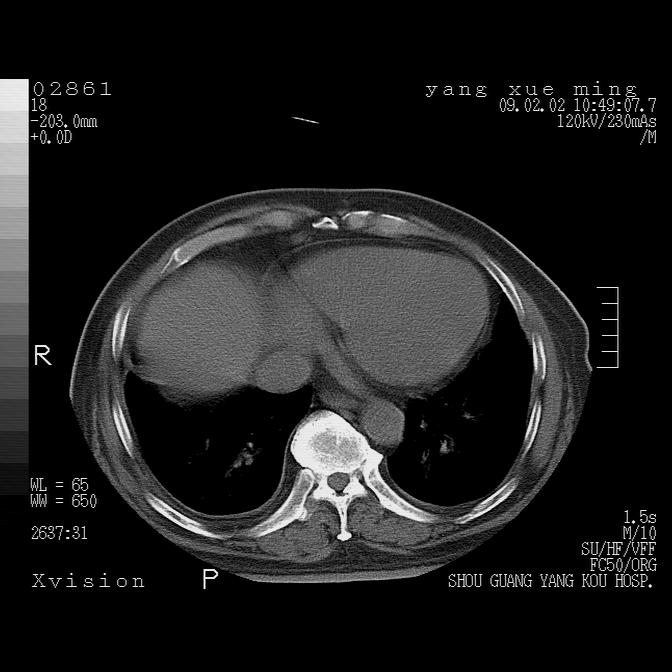

以下是引用lkc8963在2009-2-3 20:11:00的发言:[br]1)右上肺陈旧病灶。2)右下肺团块及团片影,影像表现符合感染。3)左心增大,左冠脉钙化,符合冠心病。4)双侧肺门扩大,以左侧为著,肺动脉干略粗,左上肺局限性气肿,为谨慎起见,需除肿瘤,建议增强。

以下是引用zbp537在2009-2-3 19:08:00的发言:[br]我诊断为肺泡性肺水肿。[br]诊断依据:[br]1、心影普遍增大,肺血管增粗,并见絮状高密度影,肺门改变显著。[br]2、临床上表现胸闷咳嗽,无发烧,不是一个典型的肺部感染的病史。